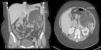

La inmunosupresión inicial fue una triple terapia con anticalcineurínicos (ciclosporina), antiproliferativos (mofetil micofenolato) y esteroides. Seis meses más tarde se modificó la pauta de la inmunosupresión, sustituyendo el mofetil micofenolato por everolimus con el doble objetivo de controlar una disfunción renal leve postrasplante y valorar la respuesta del angiomiolipoma al tratamiento farmacológico. La dosificación de los inmunosupresores se individualizó para alcanzar niveles plasmáticos cercanos a 5ng/ml de everolimus y 100ng/ml de ciclosporina. Durante su seguimiento la función renal y pulmonar permaneció estable, en estadio 0 de síndrome de bronquiolitis obliterante. Tras 6 meses de tratamiento con everolimus se solicitó nueva TC abdominal que demuestra, tras la reconstrucción, una disminución significativa del tamaño del angiomiolipoma renal (fig. 2).